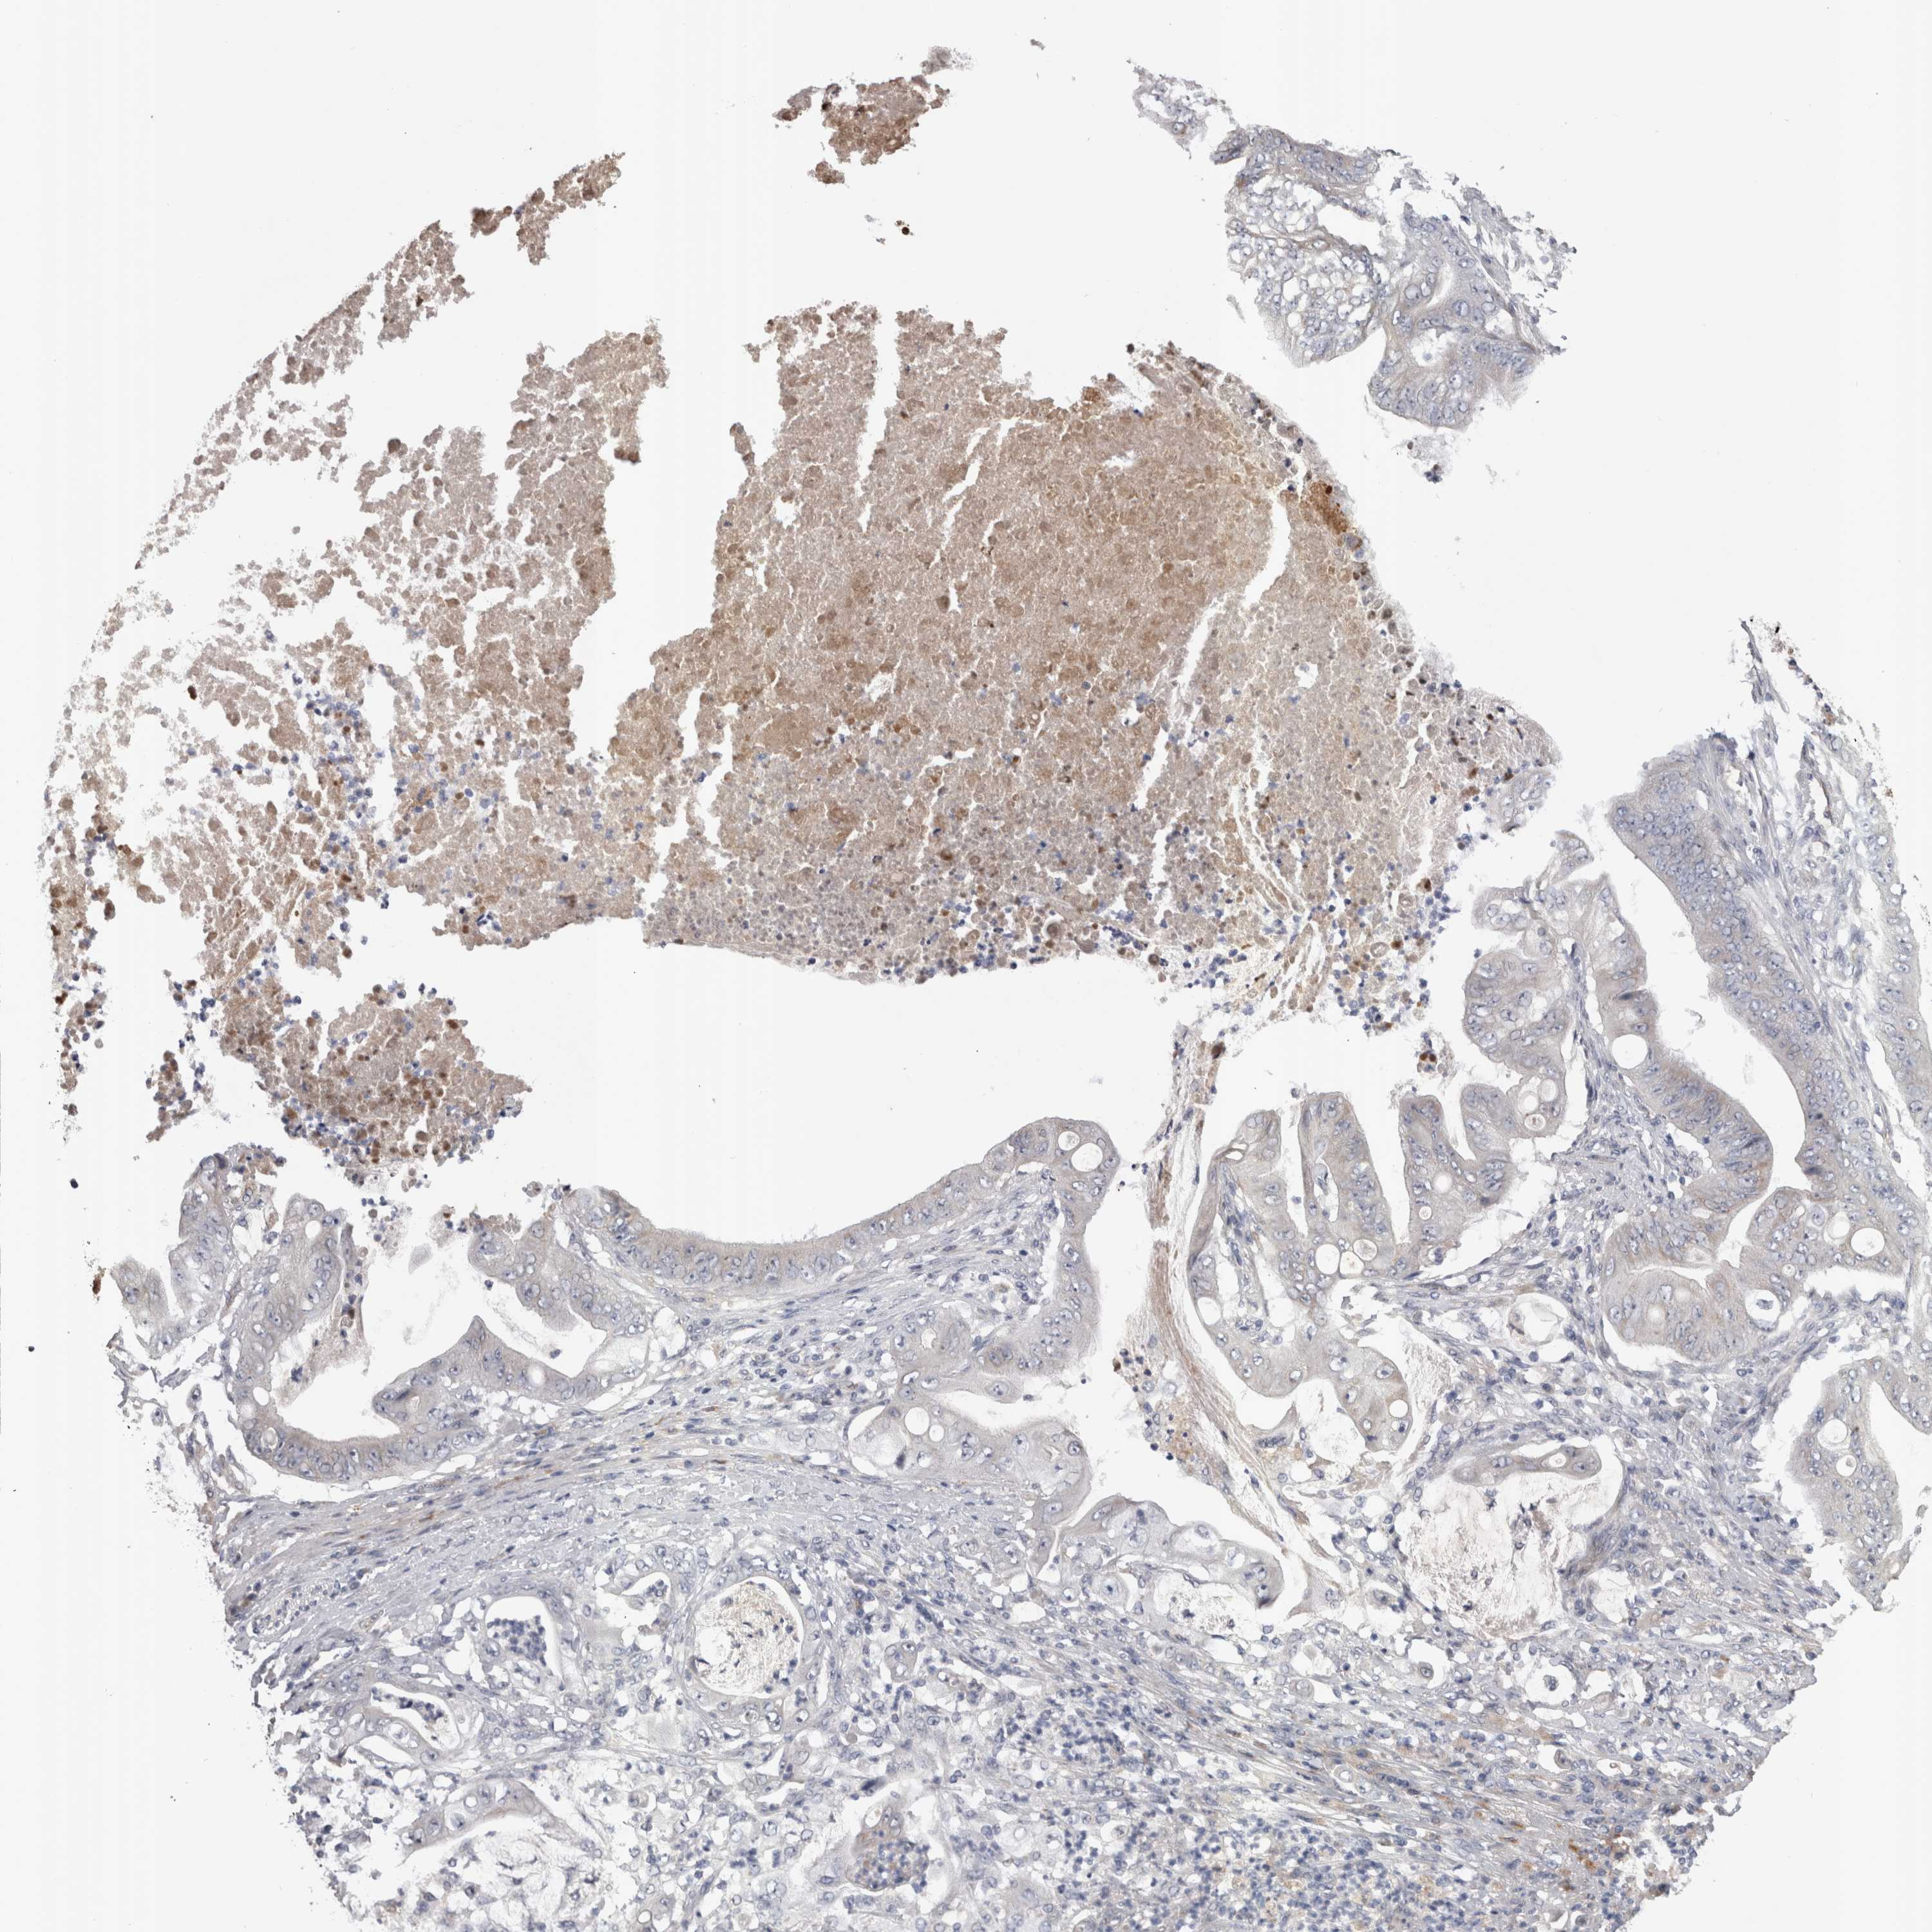

STOMACH CANCER - Protein expressioni

A mouse-over function shows sample information and annotation data. Click on an image to view it in a full screen mode. Samples can be filtered based on level of antibody staining by selecting one or several of the following categories: high, medium, low and not detected. The assay and annotation is described here.

Antibody stainingi

Antibody staining in the annotated cell types in the current human tissue is reported as not detected, low, medium, or high, based on conventional immunohistochemistry profiling in selected tissues. This score is based on the combination of the staining intensity and fraction of stained cells.

Each image is clickable and will lead to virtual microscopy that enables deeper exploration of all samples and also displays staining intensity scores, fraction scores and subcellular localization as well as patient and tissue information for each sample.

Antibody HPA023918

Antibody CAB018625

Staining

High

Medium

Low

Not detected

Adenocarcinoma, NOS